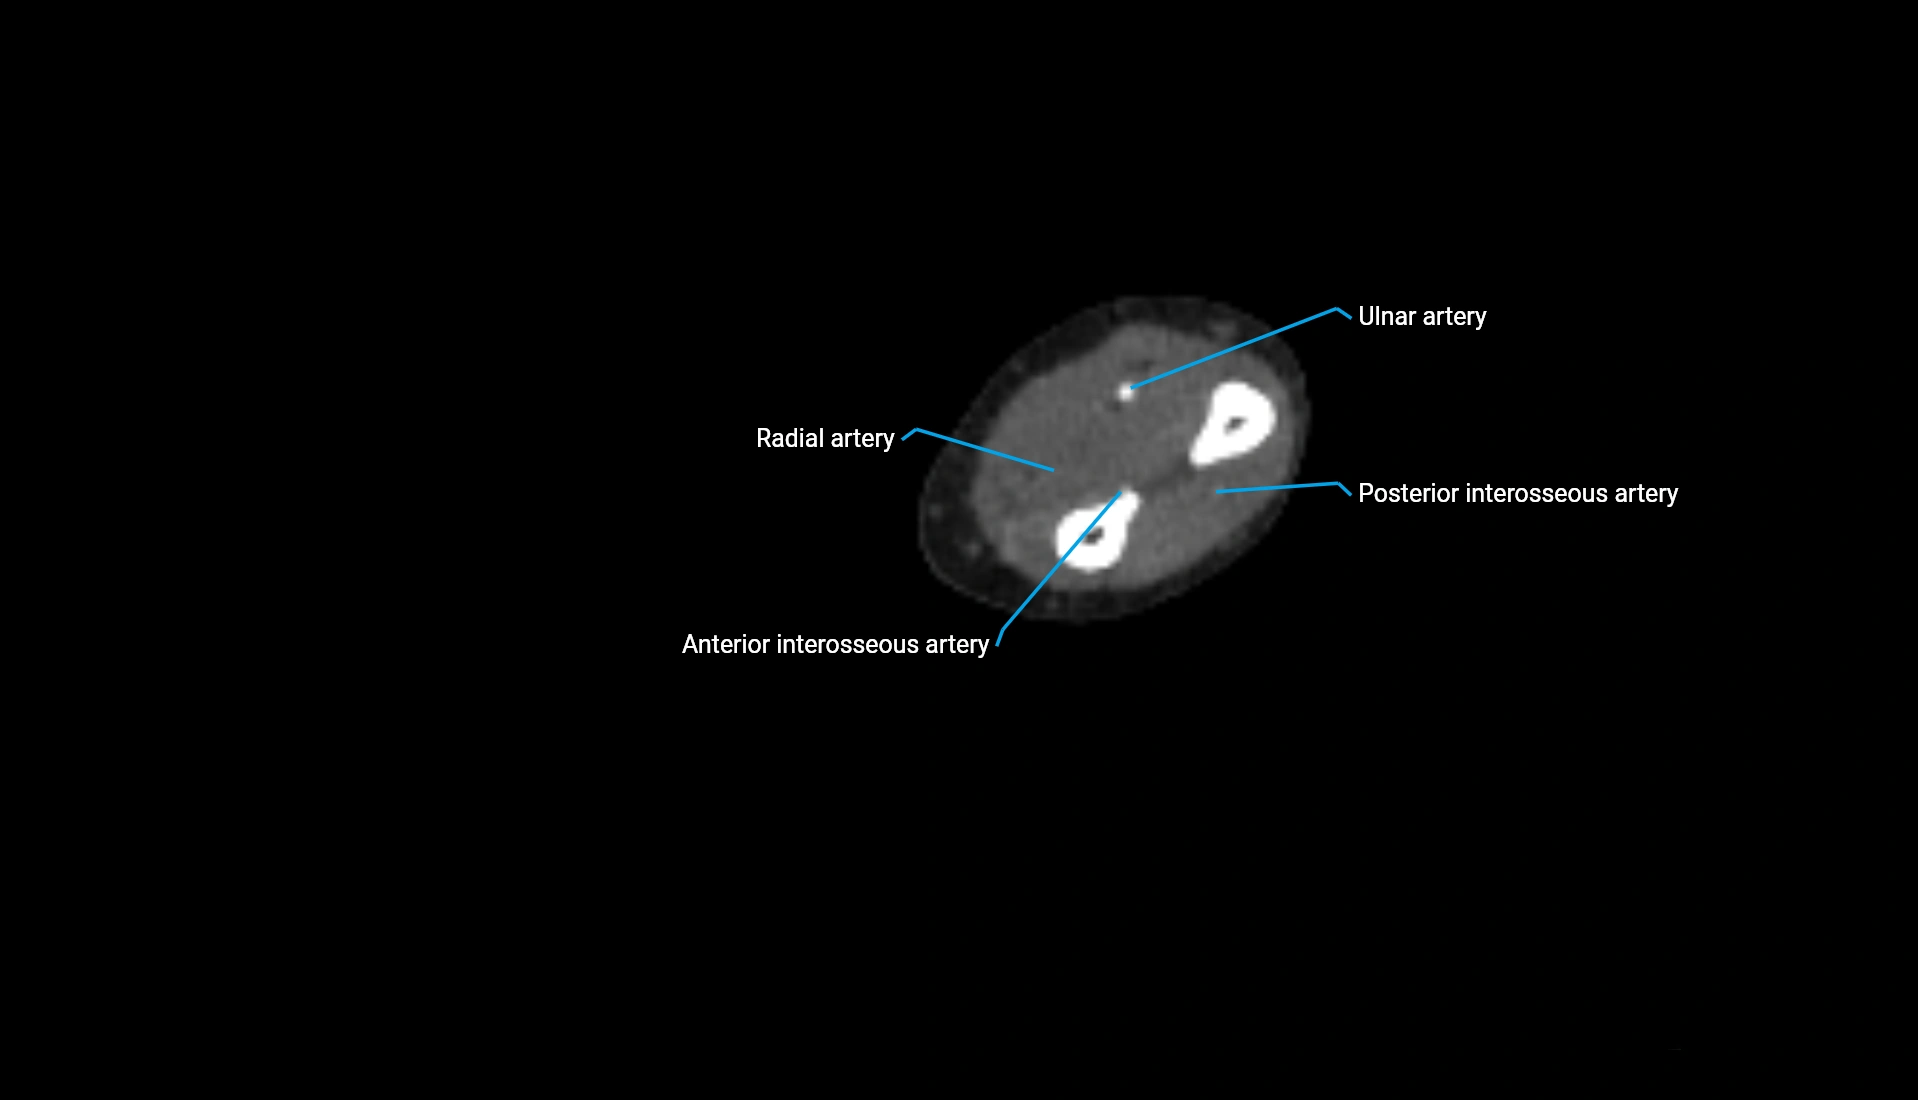

CT Appearance

Non-Contrast CT:

• Cortex: High-density, sharply defined

• Subchondral bone: Dense cancellous matrix

• Articular surface: Smooth concave contour articulating with the capitellum

• Excellent for evaluating bone integrity, alignment, and subtle fractures